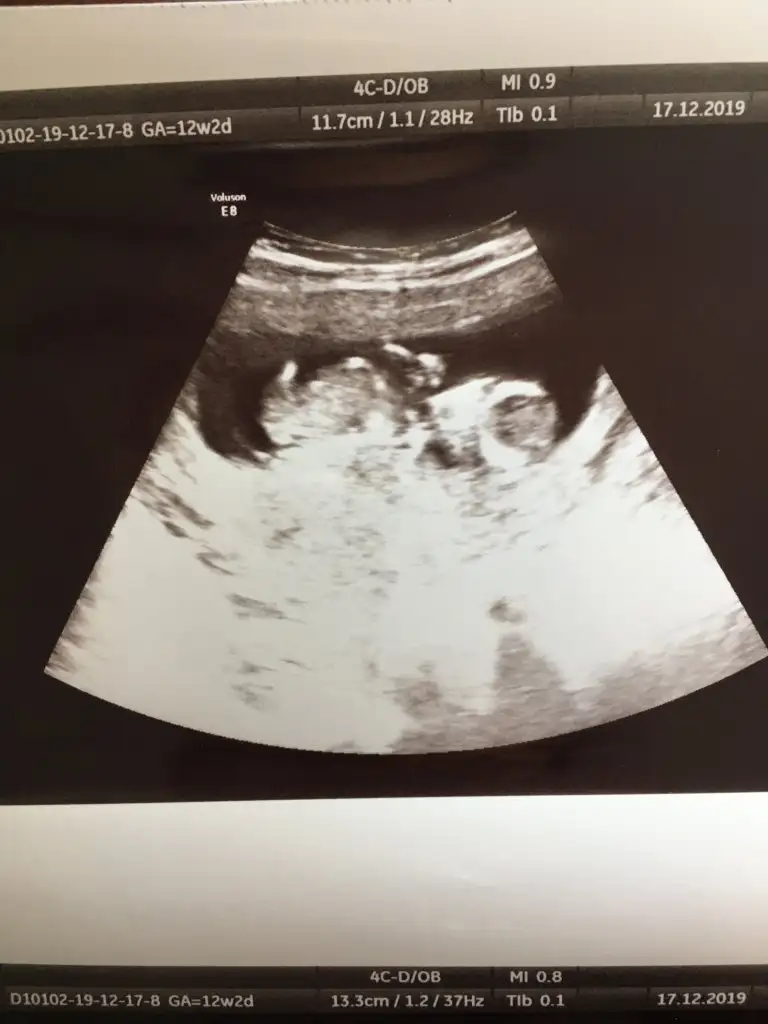

ErkekBunada bakarmisiniz 12 +2 haftalık cok merak ediyorum

Doktor %80 erkek dedi sizce net midir? Cok arkdsm

Bu haftalara guvenme her gittigimde farkli sey soyluyor doktor dedi nuba gorede erkek gibi ama merak ediyorm onceden boyle olup sonra kiz cikan var mi?

Başka usg varsa bakayım kaç haftalık usglerde tam detaylı bakamıyoruz dr daha iyi bakar biz usg de ne görürsek dr kaç haftslıkta kız dedi 11 yada 12 hafta olmalı usg nub içşnAaaaaa, ama doktor kıza benzetti ben de nedense tam olarak kız diye hissettim :) bakalım söylediğiniz çıkacak mı? :)

12+2 de kıza benziyor dedi. Başka bi tane de şu var ama pek net değil sanki.Başka usg varsa bakayım kaç haftalık usglerde tam detaylı bakamıyoruz dr daha iyi bakar biz usg de ne görürsek dr kaç haftslıkta kız dedi 11 yada 12 hafta olmalı usg nub içşn

Evet bu usgde kız paralel12+2 de kıza benziyor dedi. Başka bi tane de şu var ama pek net değil sanki.